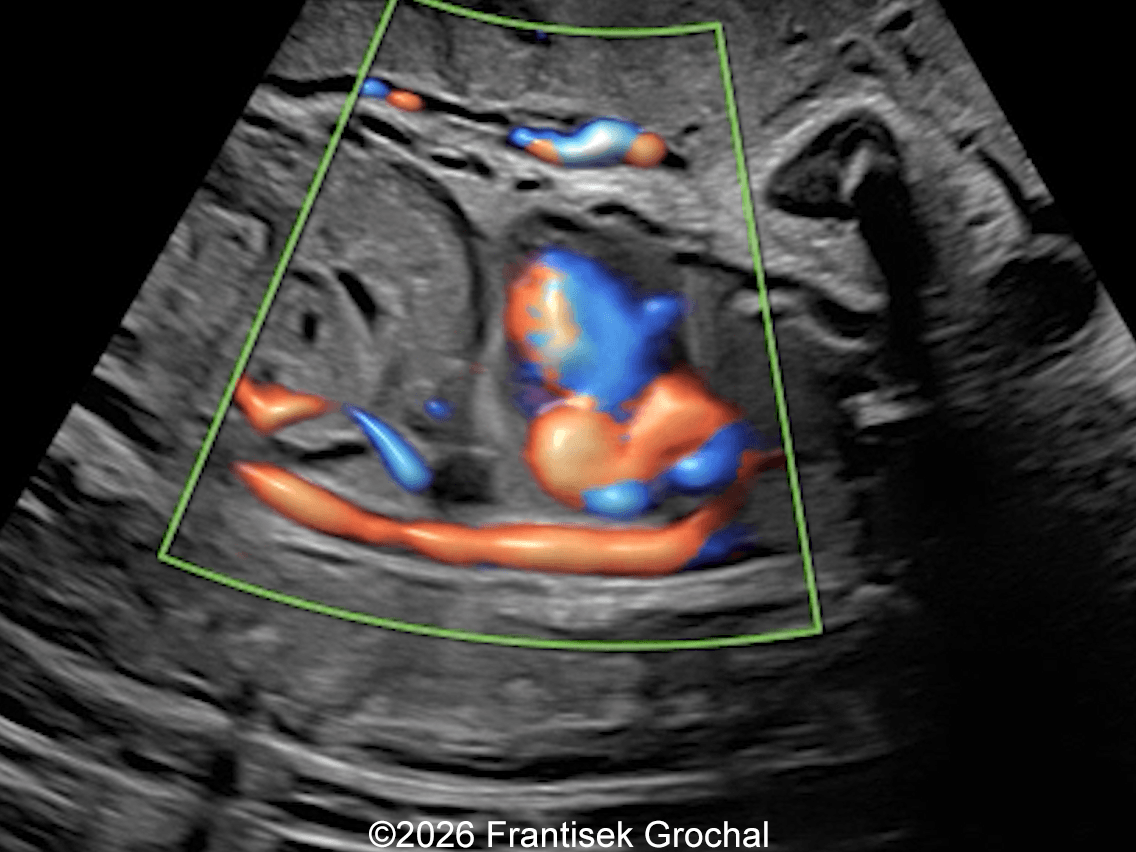

22+3 weeks of gestation – sagittal view demonstrating a well-circumscribed, triangular pulmonary sequestration; color Doppler imaging demonstrates a systemic feeding artery arising from the descending abdominal aorta.

Image 3 22+3 weeks of gestation – sagittal view demonstrating a well-circumscribed, triangular pulmonary sequestration; color Doppler imaging demonstrates a systemic feeding artery arising from the descending abdominal aorta.